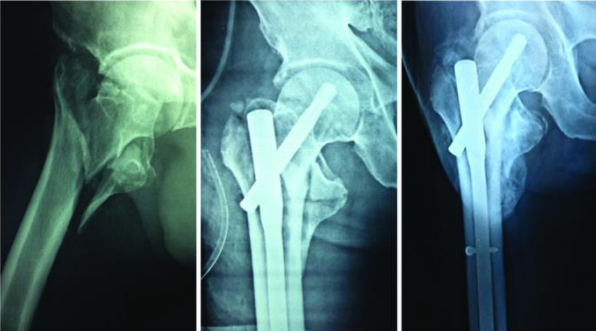

Table/Figure 4: A 31.A2 fracture treated with PFNA with good union at eight months follow up.